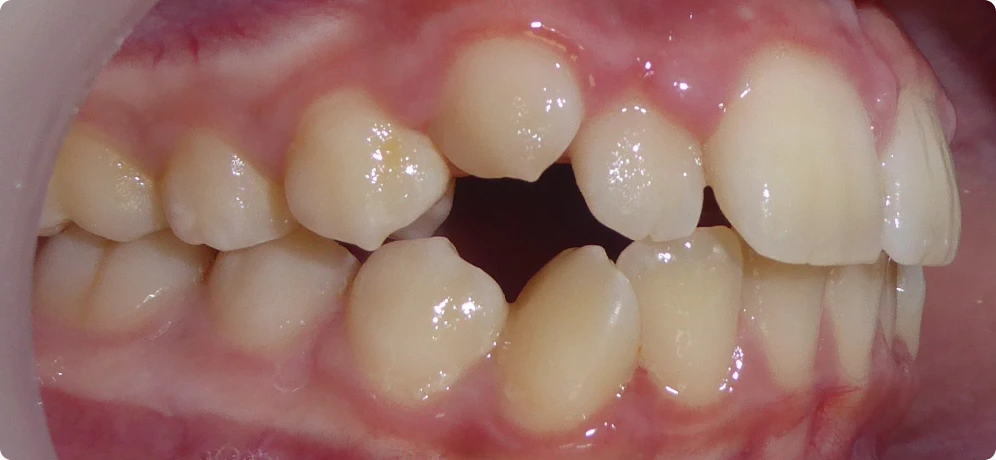

Classe I béance, adolescent, traitement Invisalign – Vue intra-buccale droite

Classe I béance, adolescent, traitement Invisalign – Vue intra-buccale de face